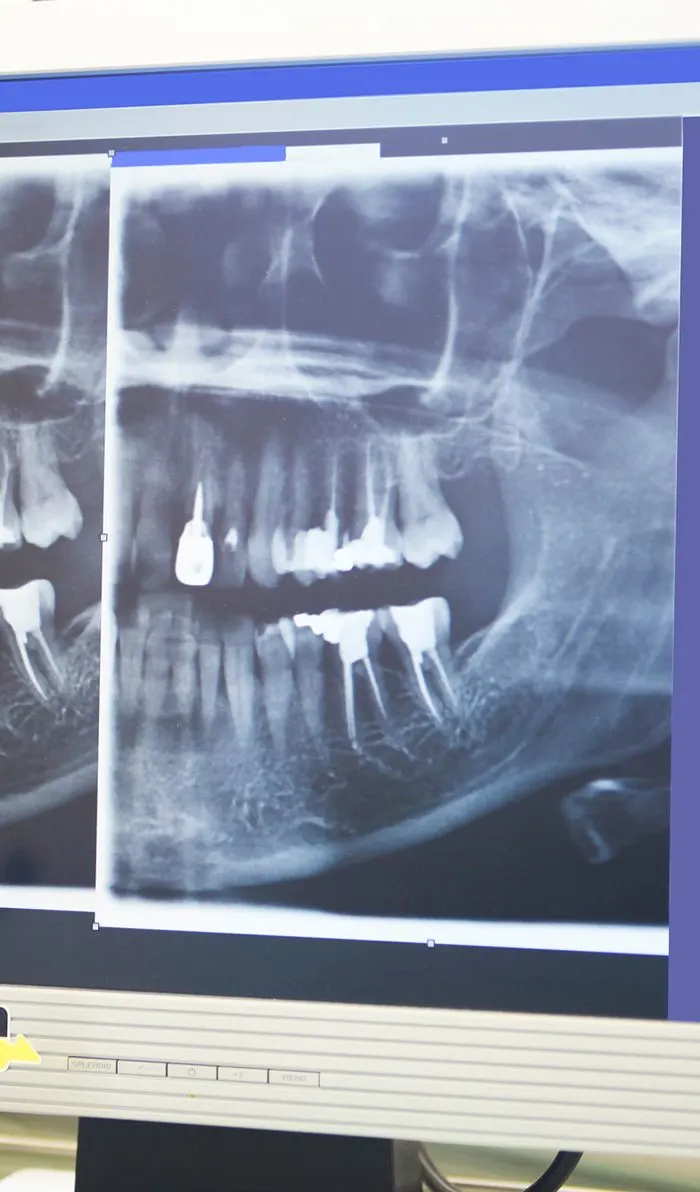

Digital Imaging

Advanced digital imaging techniques have taken the guesswork out of root canal therapy, resulting in a quicker, more efficient procedure with less pain and discomfort than ever before.

Your dentist will begin with a comprehensive examination of your tooth and x-rays to identify the cause of your dental discomfort. If an infection is present, they'll assess its severity to determine if a root canal is the appropriate treatment option.If root canal therapy is necessary, your dentist will ensure the treatment area is completely numb, including the nerves. Before starting the procedure, they'll discuss various sedation options with you to ensure your comfort throughout the treatment.